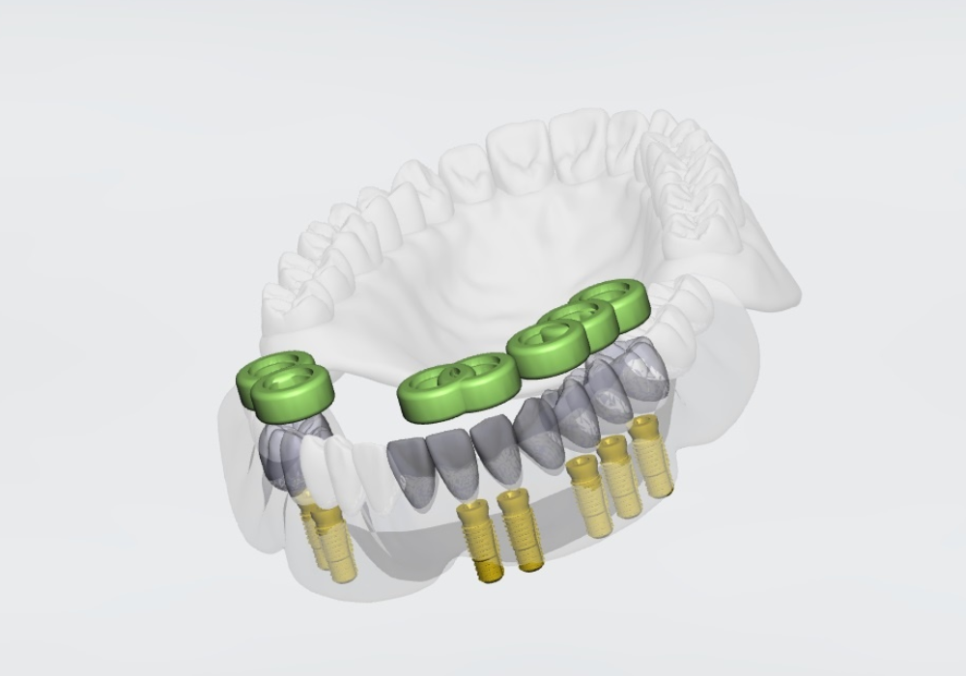

미리 만든 가이드를

입안에 고정하고 수술을 진행하니,

계획했던 위치와 깊이에 맞춰 임플란트 7개가

안정적으로 자리를 잡았습니다.

231103

심어야 할 개수가 많고 잇몸뼈 상태도

좋지 않은 어려운 조건이었지만,

가이드 덕분에 이미 정해진 위치에

오차 없이 신속하게 마무리할 수 있었습니다.

구강스캐너로 본 뜬 스캔 데이터를 통해

컴퓨터로 정밀한 보철물을 설계합니다.